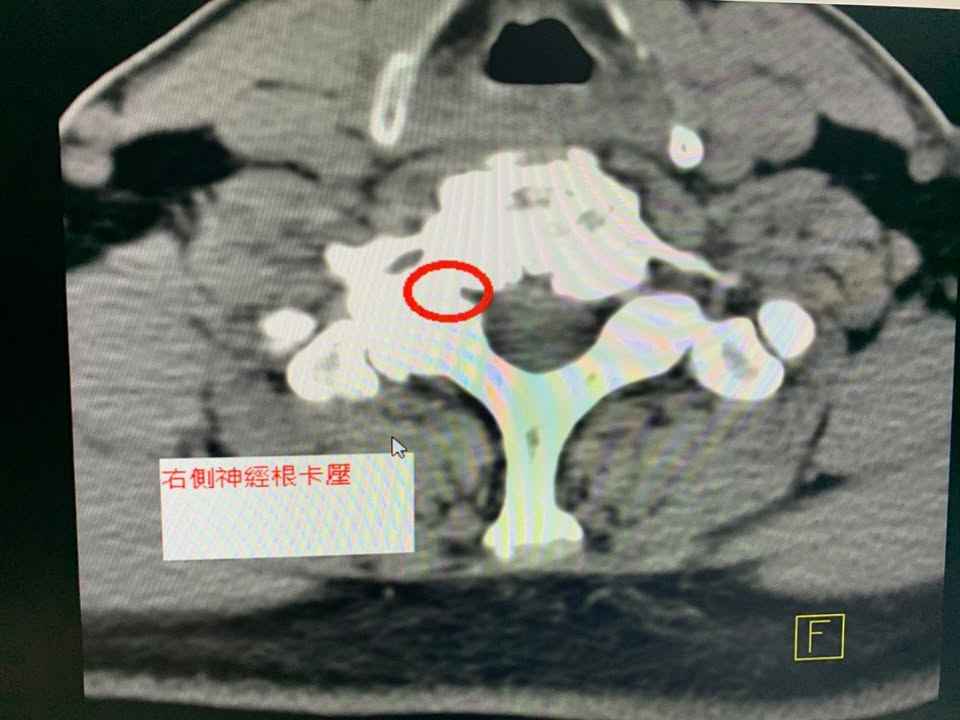

😂😂來自印尼的高先生抱怨右側肩膀非常刺痛且上臂無力與麻痛,原因是幼年的一場嚴重車禍,導致整個骨骼變形,多年來肩頸長期痠痛,一直到最近這一兩年嚴重惡化,這中間做過傳統整復,有改善但是很容易發作,今年四月在台北榮總拍攝x光片與電腦斷層CT,發現頸椎變形嚴重與椎間隙嚴重狹窄合併神經根卡壓,神外醫師建議開刀裝設人工椎間盤,但是患者畏懼開刀,經過友人介紹來接受頸椎中醫微創療法,說實在的,這是一個難度非常高的案例,多節椎間盤坍塌,椎體骨刺增生非常嚴重,頸椎弧度完全消失還變成反弓!這樣的片子看得心驚膽顫,患者抱怨右手開始變得沒力而且很容易麻痛,頭向後仰就開始疼痛,觸診頸椎肌肉跟關節面都非常緊,裡面條索筋結非常多

椎間盤突出,相鄰椎體後緣及外側緣的骨刺形成,小關節及鉤椎關節的增生肥大,黃韌帶的增厚及向椎管內形成皺摺。都可能刺激或壓迫椎管兩旁的頸神經根,引起上肢包括手指的疼痛、麻木和肌力減退等症狀